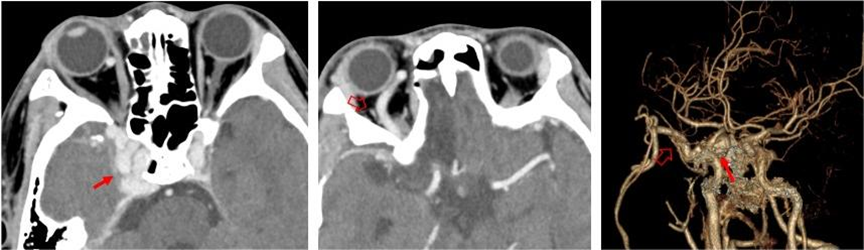

右侧颈内动脉海绵窦瘘:右侧海绵窦明显增大,血管迂曲增粗(红箭),右侧眼上静脉明显增粗(空心箭)。